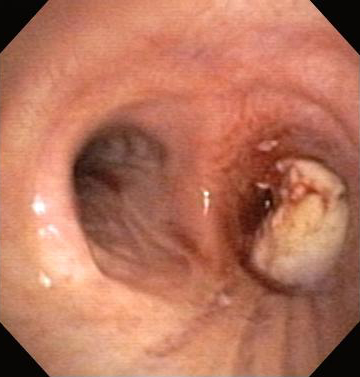

Post-lung transplant anastomotic bronchial stenosis: right mainstem anastomosis post-multimodal endoscopic therapy

From the collections of Jose Fernando Santacruz MD, FCCP, DAABIP and Erik Folch MD, MSc; used with permission